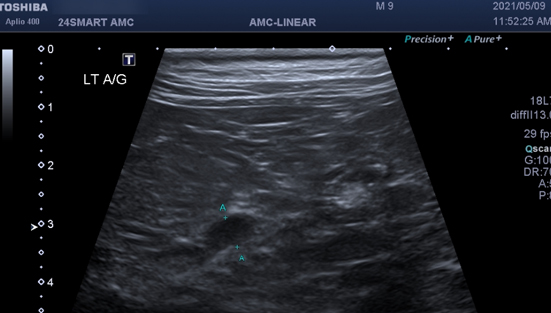

부신 질환

부신 호르몬이 과다하게 분비되어 이상을 일으키게 될 경우 부신피질기능항진증, 쿠싱 증후군이 발생하며 다음`다뇨, 탈모, 피부질환, 고혈압, 면역계 이상, 등의 합병증을 유발하게 됩니다. 부신 호르몬이 적게 분비되어 이상을 일으키게 될 경우 에디슨 질병이 발생합니다. 스트레스 상황에서 분비되어야 할 호르몬이 분비되지 못하여 대사 이상으로 인한 저혈당, 소화기 증상 등을 유발하게 됩니다.